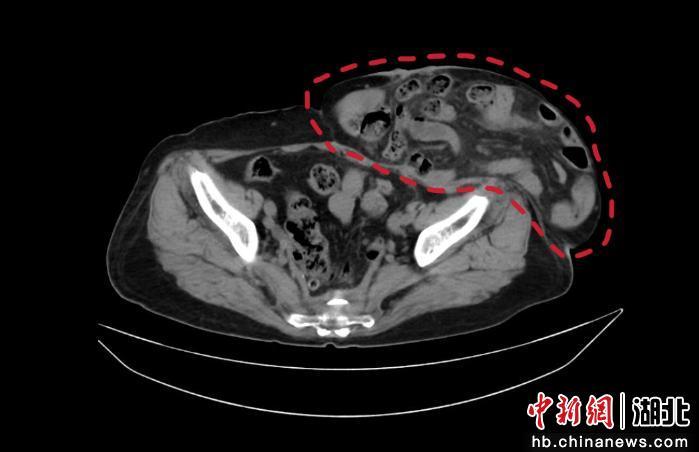

患者彭奶奶,因低位直肠癌术后13年遗留结肠造口,十年来腹壁造口旁疝逐渐增大,形如“足球”,不仅严重影响日常生活,更导致反复腹痛、排便困难、肠梗阻,甚至出现慢性肺功能受累。由于疝环巨大、腹腔内容物粘连严重,加之患者高龄、合并多种慢性病,传统开放手术需做造口移位重建,创伤大、复发率高、恢复慢,风险极高。

经过周密计划,团队决定迎难而上,采用国际先进的腹腔镜下造口旁疝修补术(Sugarbaker术式)。因患者大约30%腹腔内容物跑到造口旁疝疝囊内,直接还纳内容物,将会引起腹腔高压,进而出现心肺功能、肾功能衰竭,团队决定先给患者做渐进气腹(彩超引导下腹腔插管,注入空气)一周治疗,再手术。